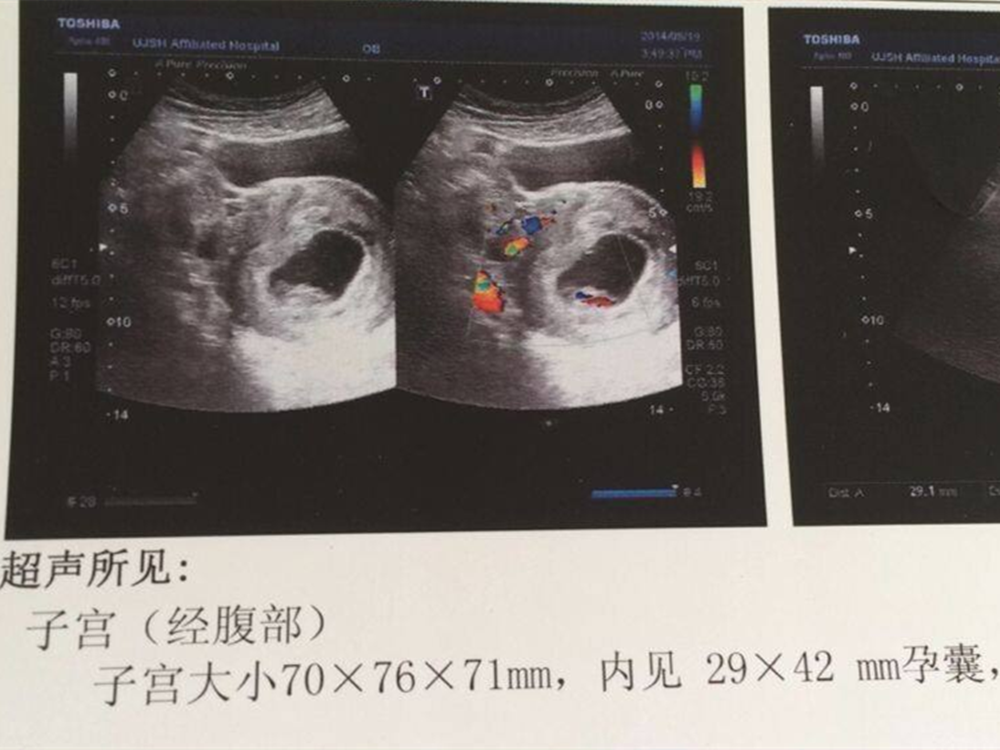

一.胚囊:

对大部分月经规律的孕妇来说,停经在五周左右时就能看到胚囊了。

而且,随着停经的时间越来越长,胚囊的形状和尺寸也会发生较大程度上的变化。停经五周后再过几天,胚囊内部还会有一种叫做“卵黄囊”的物质。

不过,有时当宫腔出现积液,可能也会造成出现胚囊的错觉,这种情况也叫做“假胚囊”。

可一旦检查发现“卵黄囊”,几乎就可以完全确定这就是胚囊了。